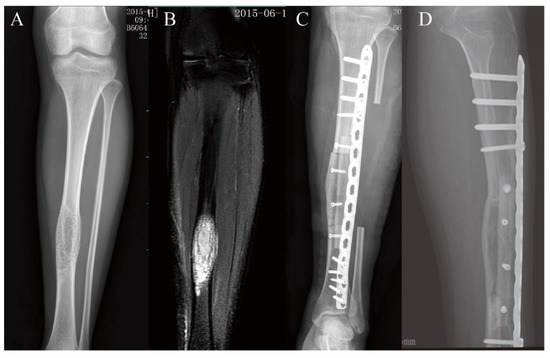

3.2. Lower Extremity Reconstruction Results

| 9 | 115 | 150 | Yes | devitalized autograft, single plate | 247 | 1000 | 42 | 6 | 29 | / |

| 10 | 120 | 150 | Yes | devitalized autograft, single plate | 180 | 600 | 69 | 8 | 27 | / |

| 11 | 110 | 150 | Yes | devitalized autograft, single plate | 180 | 300 | 59 | 6 | 30 | / |

| 12 | 95 | 130 | No | devitalized autograft, single plate | 90 | 500 | 72 | 5 | 30 | / |

| 13 | 155 | 180 | Yes | devitalized autograft, single plate | 300 | 850 | 94 | / | 23 | Nonunion |

| 14 | 110 | 147 | Yes | devitalized autograft, single plate | 240 | 300 | 89 | 6 | 28 | / |

| 15 | 115 | 150 | Yes | devitalized autograft, single plate | 240 | 300 | 123 | 5 | 22 | / |

| 16 | 70 | 130 | Yes | devitalized autograft, single plate | 240 | 300 | 73 | 3 | 30 | / |

| 17 | 90 | 130 | No | devitalized autograft, single plate | 158 | 500 | 82 | 8 | 24 | / |

| 18 | 90 | 130 | No | devitalized autograft, single plate | 180 | 300 | 79 | 6 | 28 | / |

| 19 | 120 | 150 | Yes | devitalized autograft, single plate | 240 | 500 | 74 | 6 | 28 | / |

| 20 | 90 | 130 | No | devitalized autograft, single plate | 235 | 300 | 38 | 7 | 27 | / |